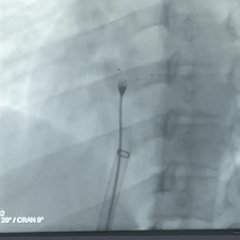

术中复测及封堵策略:术中超声复测缺损大小约19.1×17.9mm,经综合评估后,决定经股路径介入,选择BDASD-I 28可降解封堵器、16F可降解封堵器介入输送系统进行封堵,手术全程通过超声+DSA引导进行。

DSA下,左盘3个及腰部1个mark点推出,左盘展开,牵拉成型线,辅助左盘成型

后撤钢缆和鞘管,使左盘贴靠房间隔

DSA下,封堵器5个mark点随着牵拉整体移动

前抵鞘管,逆时针旋拧钢缆,封堵器释放,DSA下,5个mark点相对位置不变